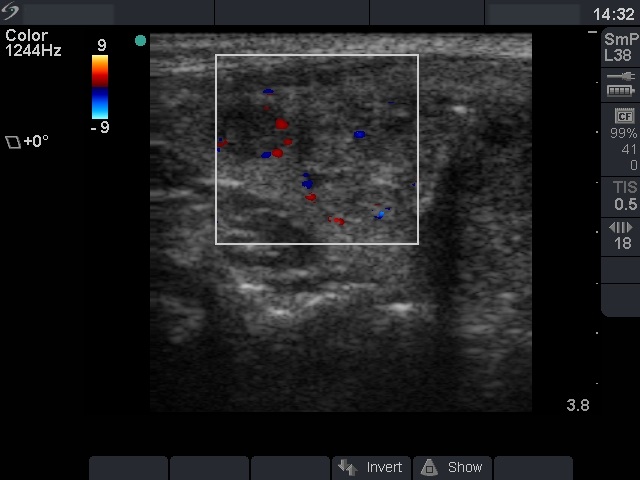

Ultrasonography: the basic echo structure of the thyroid was normal. There were three lesions in the right, and one lesion in the left lobe. The hypoechogenic one in the upper pole of the right lobe was aspirated.